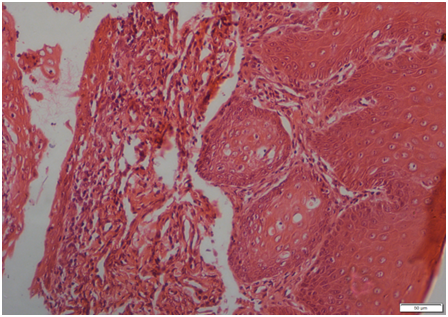

Histologically, all but one tumour were diagnosed as fibromatous epulis. The microscopic features of the fibromatous epulis consisted predominantly of cellular fibroblastic connective tissue which often interwoven with a loose connective tissue and superficial layer of the squamous epithelium having irregular projections. The capillaries were located within the looser connective tissue and there was some focuses of collagenous matrix were also present (Figure 4A). The histopathological examination in one case of lower jaw epulis revealed acanthomatous epulis, which were characterized by consist of islands and cords of squamous epithelium that have invaded irregularly in adjunct of connective tissue. Basal columnar cells were arranged with their long axes perpendicular to the basement membrane, and some exhibited vacuolated cytoplasm. These basal cells typically surrounded by sheets of squamous epithelium having intercellular bridges (Figure 4B).

Figure 3(A) Photomicrograph of fibromatous epulis (H&E x 200).

Figure 3(B) Photomicrograph of acanthomatous epulis (H&E x 200).